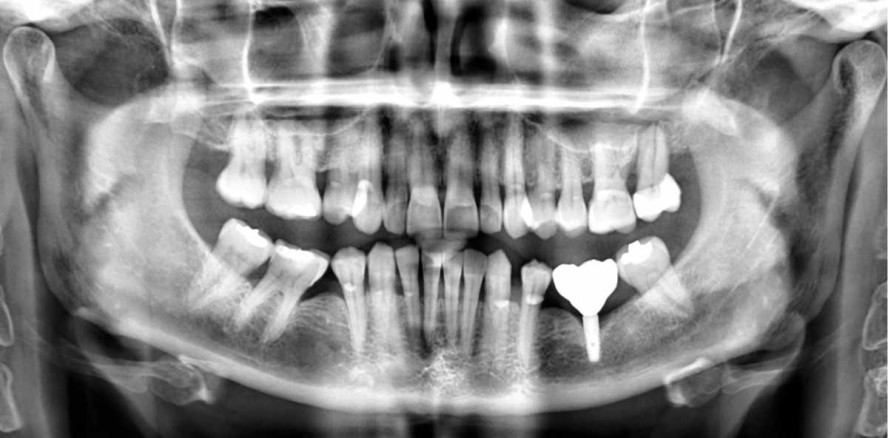

Eine 52-jährige Patientin suchte Hilfe im Klinikum aufgrund von Problemen mit ihrem Implantat in Regio 36, das in einer anderen Praxis vor ungefähr sechs Jahren eingesetzt wurde. Es schien eine Implantatlockerung zu entstehen. Auf dem OPG (ProMax, Planmeca) war ein großer Knochenverlust um das Implantat herum sichtbar, der durch Periimplantitis verursacht wurde (Abb. 2). Daher wurde das Implantat entfernt und der Defekt exkochleiert. Nach drei Monaten wurde eine CBCT-Aufnahme (ProMax, Planmeca) für die Planung eines neuen Implantatersatzes erstellt (Abb. 3). Nach Abwägung aller Optionen (vertikale Augmentation, Kurzimplantat) wurde ein anguliertes Implantat ausgewählt, das so inseriert wurde, dass es an dem Verlauf des Mandibularkanals vorbeigeht (Abb. 4). Mithilfe des CBCT-Scans wurde die Position des Mandibularkanals genauer bestimmt. Der geeignete Durchmesser und die Länge des Implantats wurden dann im Programm gewählt. Die Implantatposition wurde so festgelegt, dass das Implantat am Kanalverlauf vorbeigeht und gleichzeitig das aktuelle Knochenangebot berücksichtigt. Es ist sehr wichtig, die Situation aus verschiedenen Blickwinkeln zu betrachten, um sicherzustellen, dass die Behandlung richtig geplant wurde.